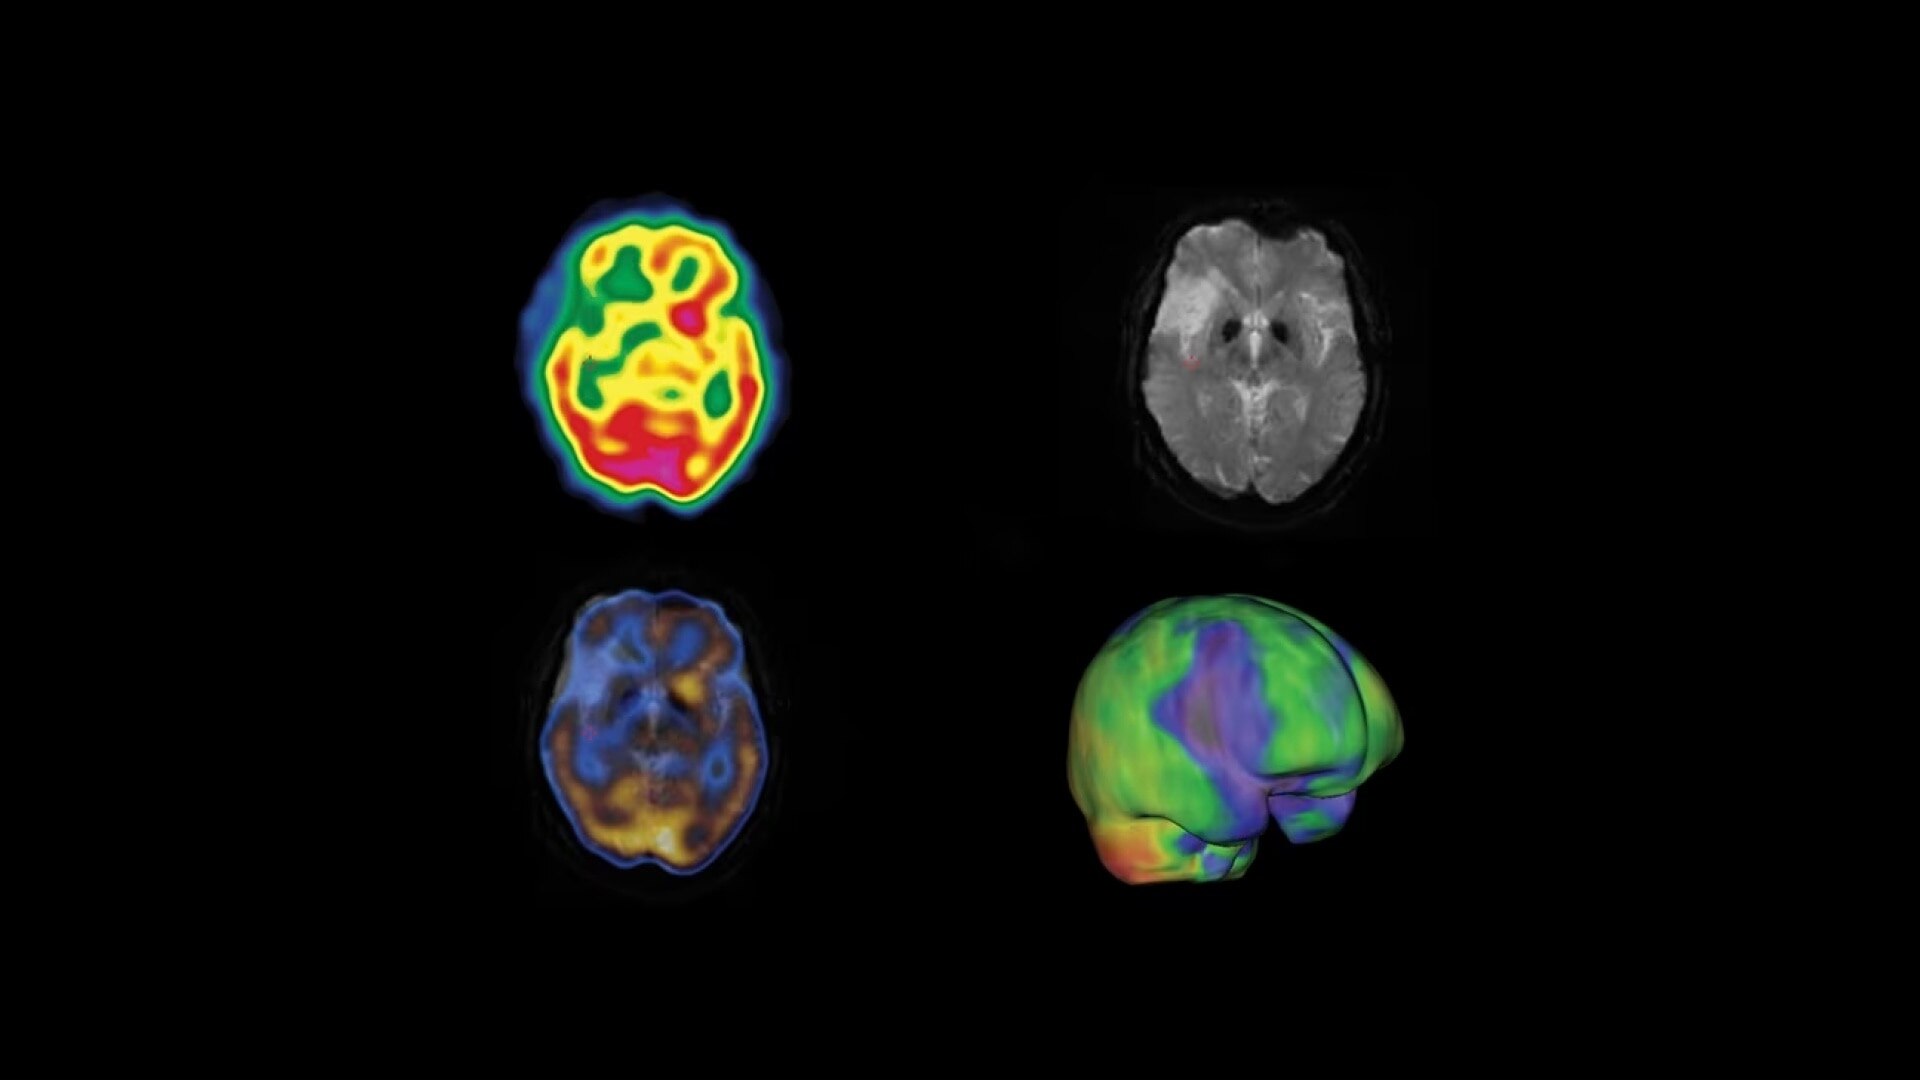

A fully digital vision for nuclear medicine

NM/CT 870 DR, working alongside our Xeleris workstation, delivers on this vision with a platform that’s ready today to leverage software innovation capable of collecting data to help develop new insights with quantitative analytics. And its modular design makes transitioning to digital detection as simple as exchanging the detector technology.

Additionally, this is a premium SPECT/CT system that delivers the added flexibility of a standalone CT that includes advancements in dose and metal artifact reduction. And it delivers the accurate, reproducible results referring physicians require in a comfortable and streamlined exam experience.